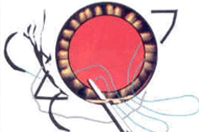

緑内障の患者様では、その患者様の病気によって各種術式が選択されます。

白内障手術同時線維柱帯切除術(左)や白内障同時Alcon社製ExPRESS手術(右)

最近では白内障同時の極低侵襲緑内障手術 iStent手術(右)が保険診療で手術ができるように認定されました。

その他CTR手術(左)・瞳孔形成術・眼内レンズ入替術・裂孔閉鎖術・Add-onレンズ挿入術・眼内レンズ回転術など手術をいろいろなデバイスや術式で行っております。